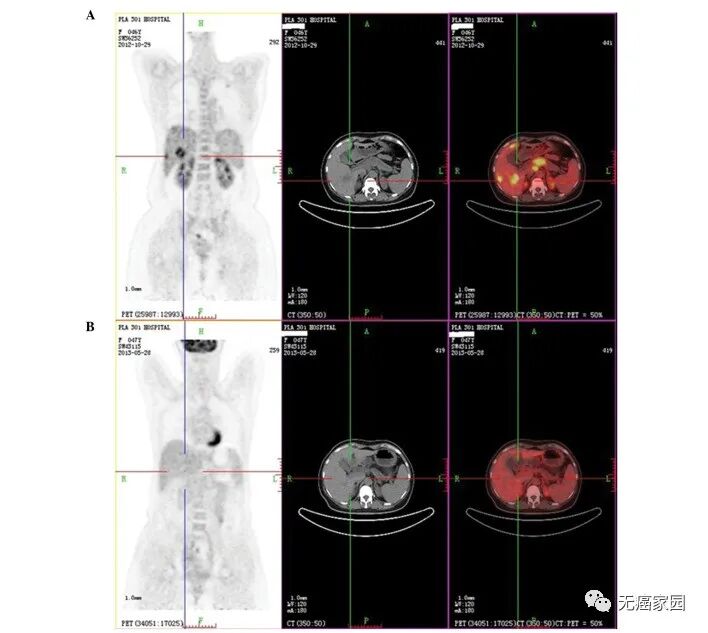

在两次输注 EAAL并结合化疗加靶向治疗的一个周期后,评估了患者的反应。2012 年 12 月的 CT 扫描显示胰腺、肝脏、肺部和腹部淋巴结的病灶略有缩小。此外,CA 19-9 水平从 4,136 U/ml(治疗前)降至 758.50 U/ml,根据 RECIST 标准,患者病情稳定。

患者继续接受6次EAAL输注,并结合3个周期的化疗加靶向治疗。通过 CT 扫描评估反应,显示肺部和肝脏的转移性病灶明显减少,胰腺中的病灶略有减少。此外,CA 19-9水平降至113.6 U/ml并实现了部分缓解 (PR)。

最后,患者又接受了6次大剂量(200ml)EAAL输注以及3个周期的化疗加靶向治疗。进行PET/CT评估反应,显示几乎所有沉积物的代谢值均显著降低甚至消失;此外,所有病变的大小都显著减小,CA 19-9水平降至24.09 U/ml(正常范围:0.1~37 U/ml) 和部分缓解以及接近完全缓解 (nCR)。

(A) 第1周期化疗加靶向治疗前患者的正电子发射断层扫描/计算机断层扫描和 (B) 第 8 周期化疗加靶向治疗联合 14 次输注扩增活化同种异体淋巴细胞治疗后,胰腺、肝脏和腹部淋巴结沉积物的代谢值明显下降,甚至消失。此外,与治疗前的病变大小相比,肺部沉积物以及所有病变的大小都显著减少。

2013 年7月的最后一次随访揭示了一种静态非进展性疾病,无进展生存期 (PFS) 为8个月,并证明所有参数,包括肿瘤标志物,都在其正常范围内。在 EAAL后偶尔会观察到轻微的不适出血。